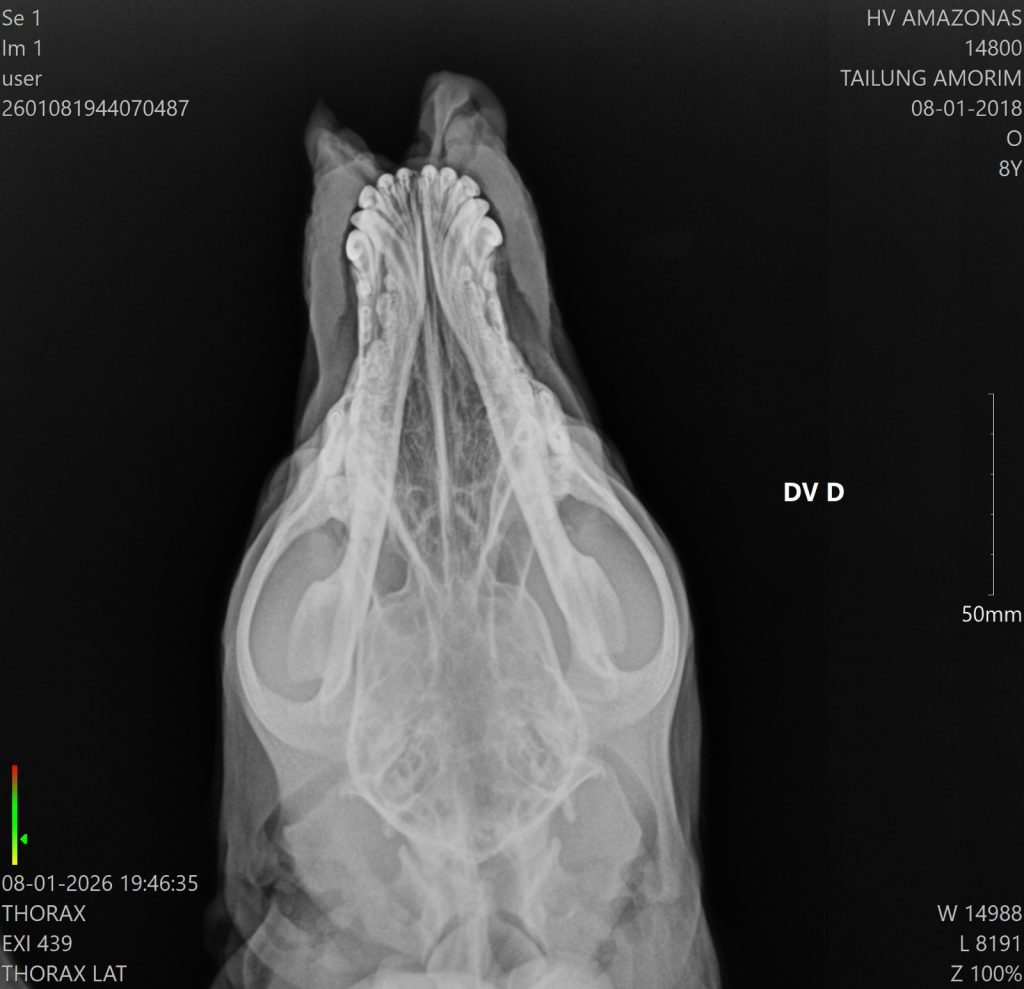

Segundo a equipe do HPVet-AM, o cachorro apresentava uma lesão profunda no focinho, causada pela terçadada. Mesmo assim, ele permaneceu consciente e reagiu bem ao atendimento.

Além disso, os profissionais concluíram a cirurgia com sucesso, e o tutor levou o animal para casa, onde ele permanece em observação. Paralelamente, a equipe multidisciplinar do hospital continua monitorando a evolução do quadro.